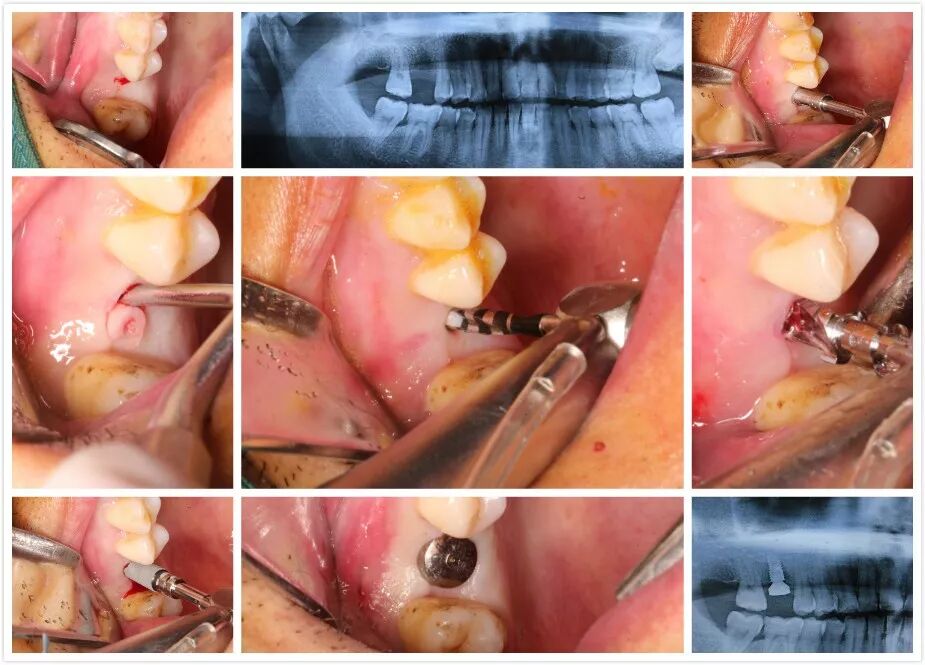

1 讲师简介 梁光强老师 (毕业于首都医科大学) 2 课程安排 第一天 1、口腔种植的基本概念 2、口腔门诊开展简单种植应该了解的基础知识 3、拓展种植牙业务医患交流技巧 4、民营口腔如何开展种植牙项目 5、开展种植所需要的设备,耗材以及所需要的准备工作 6、种植体的表面处理 7、如何读懂X光片 8、种植术前的评估--步骤与方法 9、缝合原则 10、{实习操作}缝合练习,种植X片的现场评估 第二天 1、种植牙手术术前准备 2、种植牙术中,术后的注意事项 3、种植手术植入流程 4、修复方式选择 5、印模技术 6、种植二期上部结构修复 7、门诊观看种植牙手术 8、{实习操作}种植植入模型实际操作 第三天 1、种植牙修复的并发症及处理方式 2、简单上颌窦提升技术 3、即刻种植 4、{实习操作}种植修复二期取模实际操作 3 病例展示 病例一 4 招生信息 主题:《走进民营-快速开展种植牙》 时间:2022年3月8日—3月10日 地点:宗言公司 主讲:梁光强老师 费用:老学员3600元/人(不含税)新学员3800元/人(不含税) 主办方:宗言牙材 注:公司站学习免费提供食宿 专车接送 长按二维码关注我们 更多精彩内容尽在 www.zongyan.com